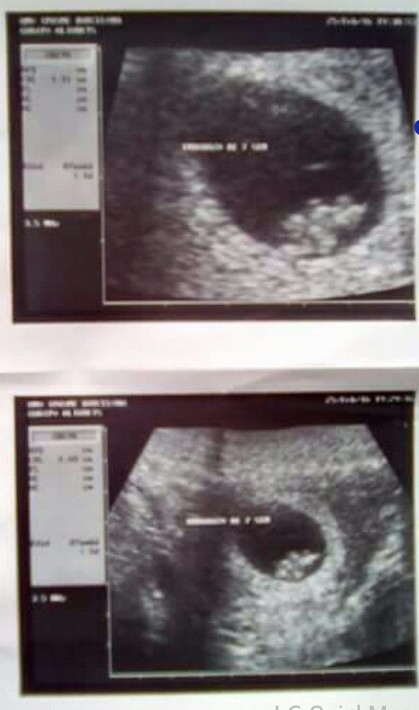

La primera visita al Gineco-Obstetra es la más emocionante, aunque no logres ver casi nada en el monitor, no hay nada más hermoso que escuchar su corazón latir y saber que se encuentra bien.